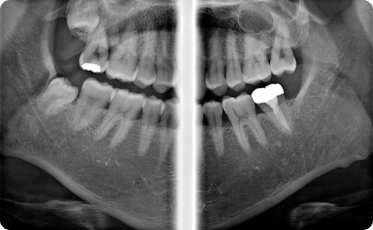

Технологии Ray обеспечивают самое лучшее качество и высокую чёткость панорамных снимков

Байт-Винг

Ортогональный

ВНЧС